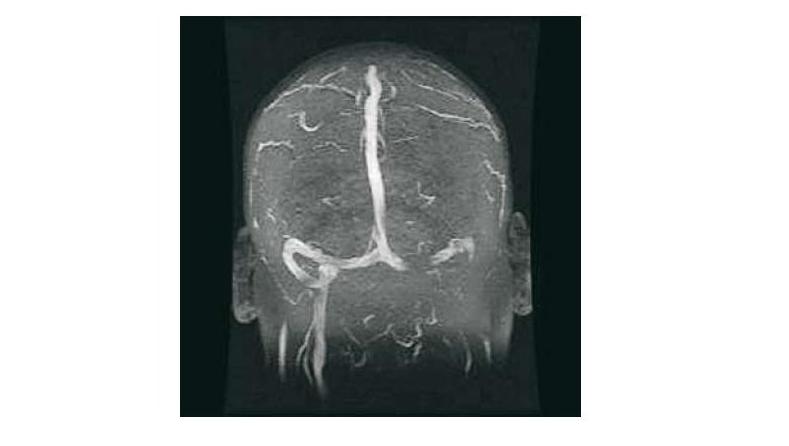

Nueva guía para el diagnóstico y tratamiento de la trombosis venosa cerebral

En esta patología, mucho menos frecuente que la enfermedad cerebrovascular de causa arterial, las evidencias son también menos concluyentes. La European Stroke Organization actualiza sus recomendaciones y señala las áreas de incerteza. European Journal of Neurology, agosto de 2017